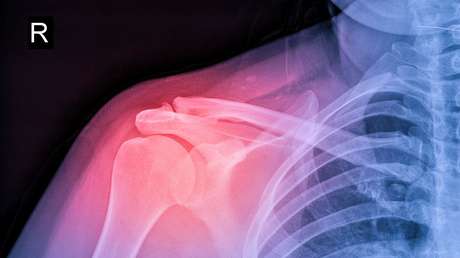

El trasplante tuvo éxito y una de las ratas necesitó ocho semanas para regenerar el hueso, mientras otras necesitaron alrededor de 12 semanas. Además, la investigadora afirmó que las pruebas demostraron que el nivel de toxicidad del procedimiento médico realizado es bajo.